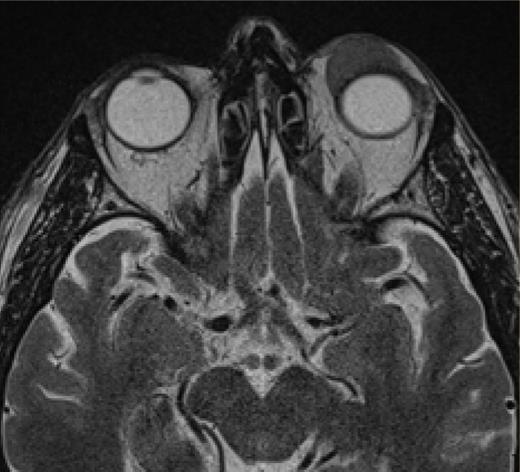

Axial MRI showing a lesion in the extraconal compartment of the left orbit.